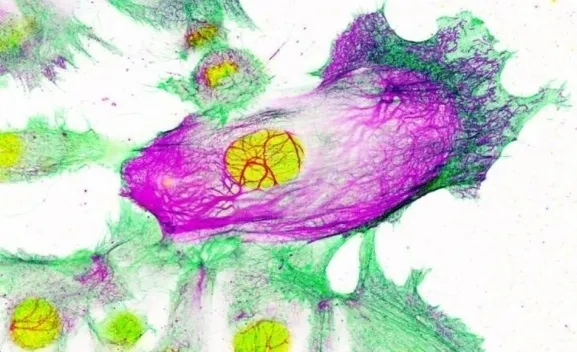

Este hallazgo, que se acaba de publicar en la revista 'Nature Communications', han descubierto que la enzima FASN, cuyos niveles se encuentran elevados en numerosos tipos de cáncer, es crucial para que se produzca uno de los procesos esenciales por el cual una célula normal se transforma en cancerosa. Bloquear FASN en un modelo animal de cáncer de mama agresivo retrasó la aparición de tumores y amplió su supervivencia en un 68 por ciento.

El equipo ha trabajado para desarrollar este proyecto con el Hospital de Fuenlabrada, Quirón de Pozuelo y el Hospital de la Princesa. En esta investigación se ha podido demostrar que cuando las células no tienen FASN, un complejo de proteínas implicadas en la síntesis de ácidos grasos, no son capaces de realizar uno de los pasos más importantes para que se formen tumores: normalmente las células de los tejidos sanos crecen en capas, bidimensionales, y cuando se amontonan suelen morir. La capacidad de amontonarse y crecer en aglomerados es una de las características de los tumores.

El grupo del doctor Quintela ha comprobado que las células sin FASN no son capaces de dar este paso fundamental en el desarrollo del cáncer. No solo eso, sino que modelos animales en los que se elimina FASN no llegan a desarrollar tumores. El bloqueo de este mecanismo ha retrasado la aparición de tumores y ampliado la supervivencia un 68 por ciento. Aunque la interrupción de la función de FASN no elimina tumores ya establecidos, estos datos tienen muchísima importancia en el campo de la prevención del cáncer de mama, abriendo una vía nunca explorada hasta el momento.